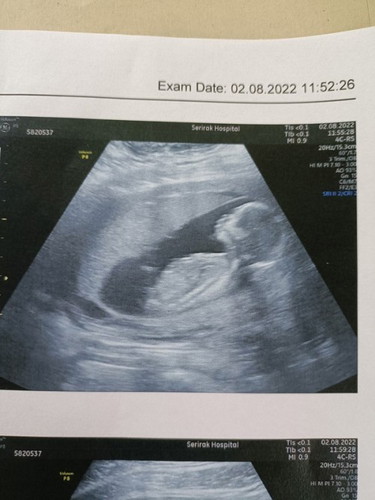

ช่วงท้อง3เดือนแรก ก่อนตรวจเจอแฟนทักว่าหน้าดูดำลงนะ หลังตรวจเจอก็เริ่มแพ้ท้องช่วงเย็นจะกินอะไรไม่ได้เลยอ้วกออกหมด (ท้องแรกลูกสาวไม่เป็นไรเลยหน้าผ่องคนทักว่าลูกสาวเยอะ) ผดเริ่มขึ้นหน้า คนทักว่าลูกชายเกือบทั้งหมดมีไม่ถึง5คนบอกลูกสาว แนบรูปซาวด์ล่าสุดตอน15วีคมาให้ค่ะ เค้าบอกเด็กตัวโตน่าจะได้ผู้ชายกัน ทุกคนคิดว่าไงคะ #ทีมมกรา66